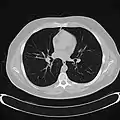

Chest CT (axial lung window)

Chest CT (coronal lung window)- Chest CT (axial lung window)